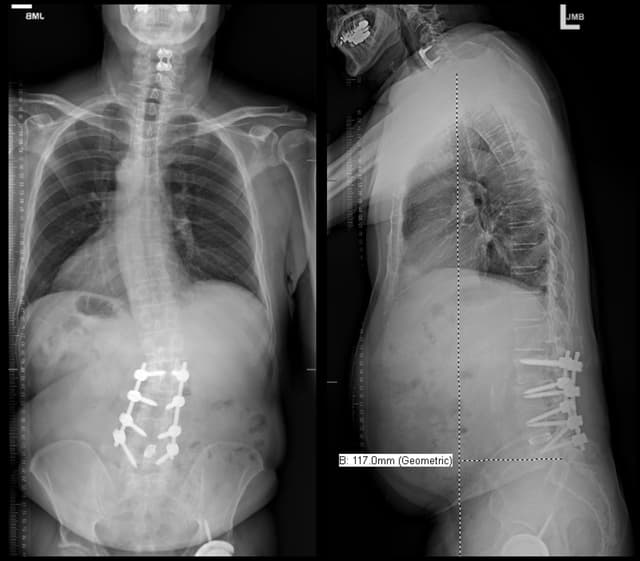

Imaging

Pre-op